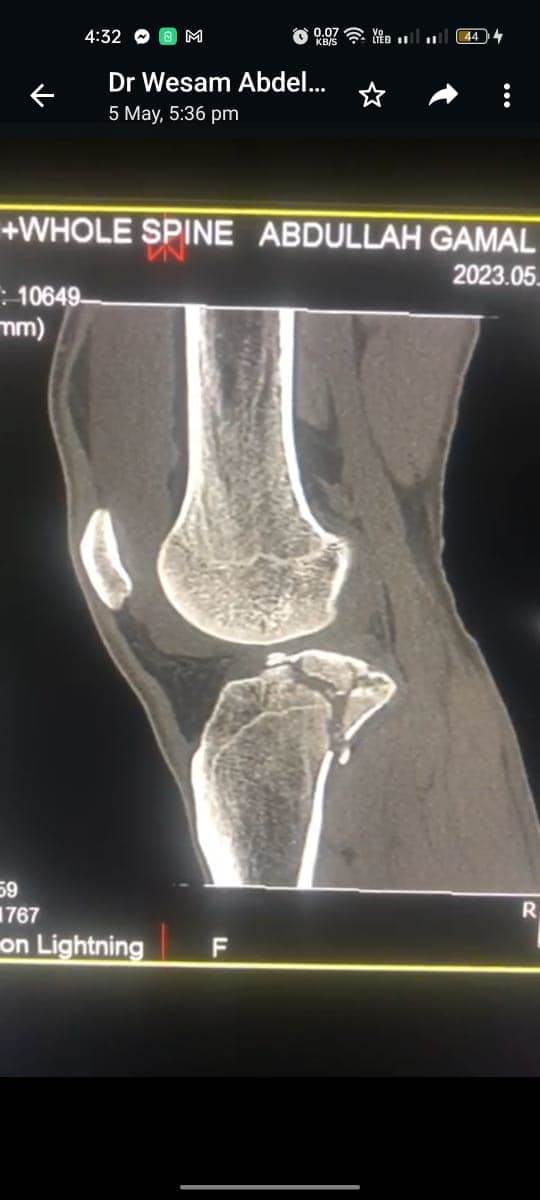

مشيرًا الى أن ذلك النوع من الكسور يكون قريبًا جدًا من الأعصاب والأوعية الدموية الرئيسية للساق والتي توجد خلف مفصل الركبة.. حيث تم الوصول الى الكسر وإعادة بناء سطح المفصل وتثبيته باستخدام شريحة ومسامير وأسلاك معدنية باستخدام جرح ٧ سنتيمترات خلف الركبة واستخدام مسامير جانبية مجوفة بدون فتح لتثبيت الجزء الخارجى من سطح المفصل، وتم الاطمئنان على الأوعية الدموية قبل إفاقة المريض، وبعد تمام الإفاقة.. تم الاطمئنان على الأعصاب والأوعية للمريض.

وأضاف أنه نظرًا لقرب هذا الكسر من سطح المفصل تم عمل أشعة مقطعية بعد الجراحة للتأكد من جودة بناء المفصل وعدم وجود أى بروز للمسامير داخل المفصل، وجارٍ تحضير المريض لعمل رنين مغناطيسى لتحديد الأربطة الداخلية والخارجية للركبة التي ستحتاج لإعادة بناء بالمنظار.